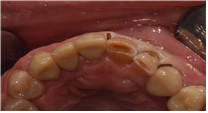

# 21, 22 치경부 마모증이 심하고 사이 충치까지 존재해 크라운 치료가 제일 심미적이겠지만, 필요한 부분만 제거하고 레진수복치료를 하였습니다.

#21.22 C.RF 절단면 RF 설명드림.

치료 후